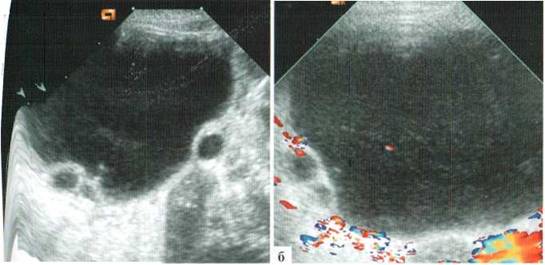

Наиболее частыми заболеваниями внутренних гениталий у новорожденных девочек являются кисты яичников. Подозрение на эту патологию возникает при обнаружении объемного образования в животе младенца женского пола при отсутствии пороков развития других органов, в основном почек. Точная идентификация патологии часто бывает затруднительна, в частности типичная локализация в нижних отделах живота встречается совсем не всегда. Высокое расположения яичника у новорожденной обусловливает возможность и высокого расположения кисты яичника — даже is подпеченочном пространстве. При этом кистозное образование в животе новорожденной может достаточно легко смещаться в стороны, соответственно четко сказать правый или левый яичник поражен, возможно не всегда (рис. 2.1).

Рис. 2.1. Киста яичника расположена на уровне почки

При крупных размерах кисты и ее высокой локализации бывает сложно эхографически установить ее органную принадлежность. В таких случаях следует, во-первых, четко визуализировать все остальные органы (если какой-либо орган не найден, возможно имеет место именно его кистозная трансформация?), а во-вторых оценить наличие или отсутствие патологических изменений обнаруженных органов (при кистозной трансформации холедоха имеется деформация желчного пузыря, при обструктивных уропатиях и кистозных дисплазиях почек возможны изменения мочевого пузыря). Возможны ситуации, когда достоверно идентифицировать органную принадлежность кисты эхографически не удается, в таких случаях в заключении должны быть сформулированы основные предполагаемые варианты.

Патогномоничным эхографическим симптомом кисты яичника является наличие мелких пристеночных внутрипросветных кист (рис. 2.2). К сожалению, частота встречаемости этого эхосимптома не превышает, по данным разных авторов, 50—70%. Внутрипросветные кисты могут быть единичными (чаше) или множественным (значительно реже), иметь диаметр от 2 до 10 мм.

Рис. 2.2. Пристеночные внутрипросветные кисты (стрелки) в кистах яичников у новорожденных:

а — единичная мелкая внутрипросветная киста (стрелка) у новорожденной с кистой правого яичника, достигающей 7 см в диаметре;

б — единичная, относительно крупная (10 мм в диаметре) внутрипросветная киста у новорожденной 16 суток с кистой левого яичника до 29 мм в диаметре